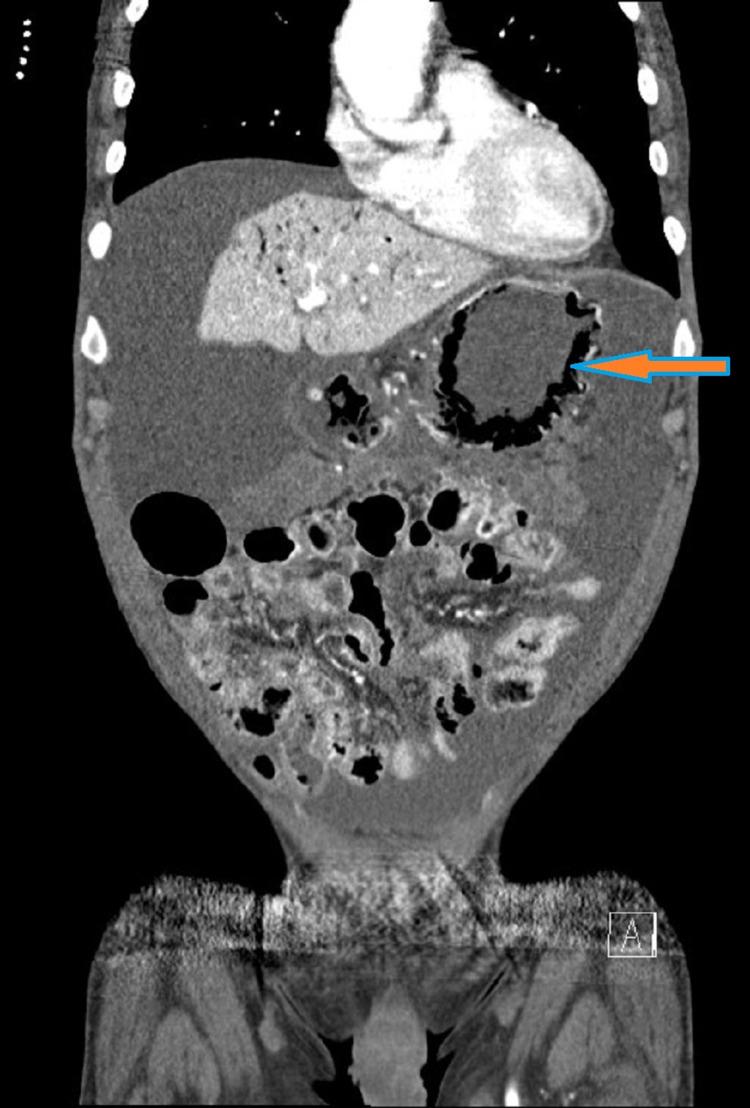

Emphysematous gastritis is a rare medical condition characterized by the presence of intra-mural air in the stomach associated with portal venous air tracking to a variable degree. There are no established guidelines favoring surgery over medical management. We present a case of a 64-year-old Caucasian male with a history of stage four colon adenocarcinoma with peritoneal carcinomatosis, malignant ascites, and liver metastasis status post-three cycles of chemotherapy who presented to the emergency room with complaints of generalized abdominal pain, nausea, non-bilious vomiting, and melena stools. He was managed conservatively as a case of sepsis secondary to emphysematous gastritis and made a full recovery. To our knowledge, this is the first reported case of emphysematous gastritis in an adult with colon cancer. Although we cannot establish a causal link between his chemotherapy regimen and emphysematous gastritis, the combined effect of an immunosuppressive state caused by advanced malignancy and cytotoxic effects of chemotherapy are the probable risk factors in our patient. We described the possible mechanisms of mucosal disruption by fluorouracil and bevacizumab in our case. Despite historically having a poor prognosis, emphysematous gastritis can be managed conservatively on a case-by-case basis. Clinicians should be aware that chemotherapy can be a predisposing factor to developing this rare condition.

气肿性胃炎是一种罕见的医学病症,其特征是胃壁内存在气体,并伴有不同程度的门静脉气体播散。目前尚无明确的指南支持手术治疗优于药物治疗。我们报告一例64岁的白种男性患者,有四期结肠腺癌病史,伴有腹膜癌转移、恶性腹水和肝转移,在接受三个周期化疗后,因出现全身腹痛、恶心、非胆汁性呕吐和黑便而就诊于急诊室。他被作为气肿性胃炎继发脓毒症的病例进行保守治疗,并完全康复。据我们所知,这是首例在成年结肠癌患者中报道的气肿性胃炎病例。虽然我们无法确定其化疗方案与气肿性胃炎之间的因果关系,但晚期恶性肿瘤导致的免疫抑制状态和化疗的细胞毒性作用的联合效应可能是我们这位患者的危险因素。我们在病例中描述了氟尿嘧啶和贝伐单抗导致黏膜破坏的可能机制。尽管气肿性胃炎以往预后较差,但可根据具体病例进行保守治疗。临床医生应意识到化疗可能是发生这种罕见病症的一个诱发因素。